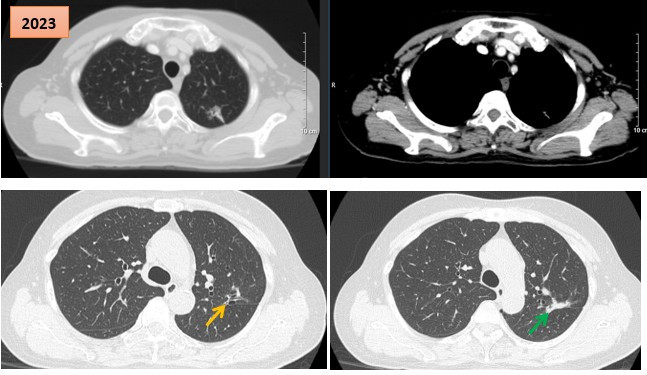

Ngày 8/1/2026 vừa qua Bệnh viện K đã ghi dấu một bước tiến quan trọng trong điều trị ung thư phụ khoa khi triển khai thành công kỹ thuật sinh thiết hạch cửa sau phúc mạc sử dụng ICG (Indocyanine Green) kết hợp phẫu thuật nội soi qua đường âm đạo (vNOTES) cho bệnh nhân ung thư nội mạc tử cung giai đoạn sớm. Đây là lần đầu tiên tại Việt Nam, kỹ thuật đánh giá hạch tiên tiến được thực hiện hoàn toàn qua đường âm đạo, tiếp cận trực tiếp khoang sau phúc mạc, không cần bất kỳ vết mổ nào trên thành bụng.

Bệnh nhân nữ 69 tuổi, có tiền sử tăng huyết áp, nhập viện vì ra máu âm đạo bất thường sau mãn kinh. Sau thăm khám và đánh giá toàn diện, bệnh nhân được chẩn đoán ung thư nội mạc tử cung giai đoạn IA.

Khi hội chẩn đa chuyên khoa, ê-kíp phẫu thuật quyết định lựa chọn phương pháp vNOTES sinh thiết hạch cửa sau phúc mạc sử dụng ICG, đồng thời cắt toàn bộ tử cung và hai phần phụ. Ca phẫu thuật do Tiến sĩ, bác sĩ Lê Trí Chinh - Trưởng khoa Ngoại Phụ khoa, Bệnh viện K trực tiếp thực hiện, phối hợp cùng ê-kíp gây mê hồi sức do Tiến sĩ, bác sĩ Trần Đức Thọ phụ trách, đã diễn ra an toàn, chính xác và thuận lợi.